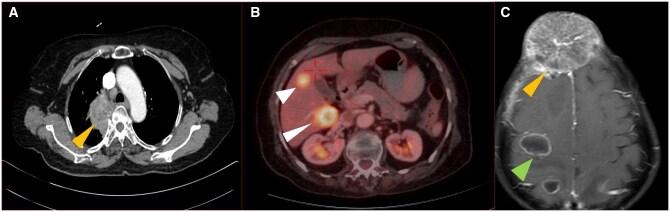

Lung cancer is the second most commonly diagnosed cancer worldwide. In the present era of targeted therapy for various lung cancer mutations, it is essential to be aware of the imaging correlates of various lung cancer mutations on contrast enhanced computed tomography of thorax. In this article, we have discussed the imaging patterns of various types of lung cancer including different mutations and also comprehensively reviewed the imaging recommendations (National Comprehensive Cancer Network [NCCN], European Society of Medical Oncology [ESMO] and American Society of Clinical Oncology [ASCO]) and management guidelines of lung cancer (non-small cell, small cell and other neuroendocrine tumours). We have also discussed guidelines for screening, diagnosis, staging (recent 9th edition tumour node metastasis [TNM]), treatment response evaluation, and follow up. Role of interventional radiology in the treatment of primary lung cancer, lung metastasis, and management of posttreatment complications, have also been described in detail in this article. In addition, current status of artificial intelligence in lung cancer has also been briefly discussed.

肺癌是全球第二大常见的确诊癌症。在当前针对各种肺癌突变进行靶向治疗的时代,了解胸部对比增强计算机断层扫描上各种肺癌突变的影像学关联至关重要。在本文中,我们讨论了包括不同突变在内的各种类型肺癌的影像学模式,并全面回顾了肺癌(非小细胞、小细胞和其他神经内分泌肿瘤)的影像学建议(美国国立综合癌症网络 [NCCN]、欧洲医学肿瘤学会 [ESMO] 和美国临床肿瘤学会 [ASCO])及管理指南。我们还讨论了筛查、诊断、分期(最新第9版肿瘤淋巴结转移 [TNM])、治疗反应评估和随访的指南。本文还详细描述了介入放射学在原发性肺癌治疗、肺转移以及治疗后并发症管理中的作用。此外,还简要讨论了人工智能在肺癌方面的现状。